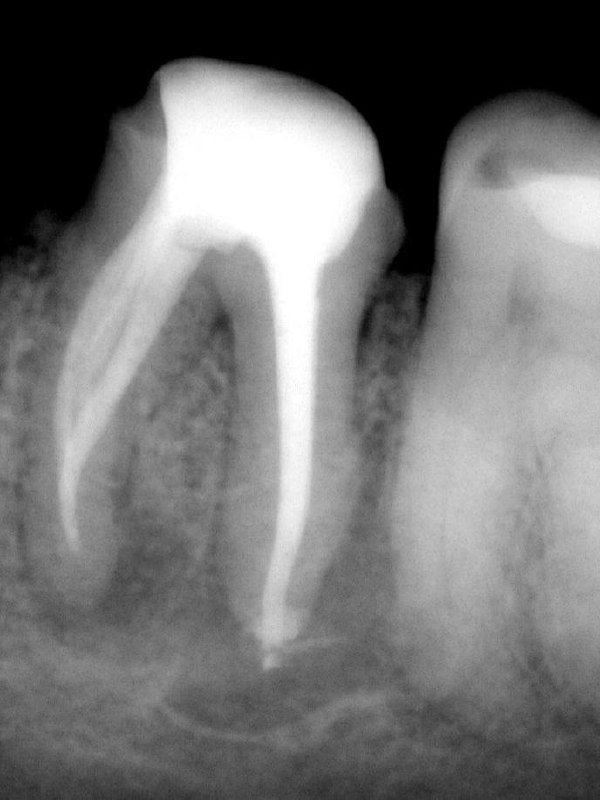

- Два анкерных штифта извлечены ✅

- Срединный мезиальный канал найден ✅

- Гуттаперча за апексом — случилось ❌

Лайфхак от Йоши Тераучи: XP-финишер, обязательно только оригинальный, чуть выводим за апекс, аккуратно работаем, и часть гуттаперчи уходит. Не идеально, но клинически — рабочее решение.